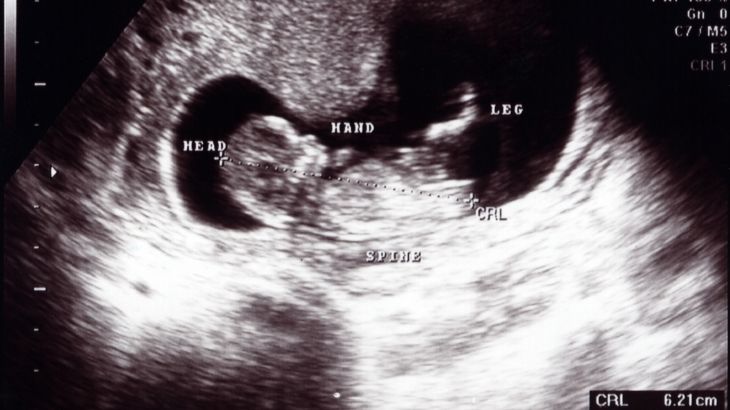

12. haftada bebeğin kalp atışları ultrason ile duyulabilir. Bebeğin kafa yapısı, omurga çizgisi ve kol–bacak hareketleri net şekilde görüntülenebilir.

Ultrason: Bebek gelişimi, kalp atışı, plasenta konumu